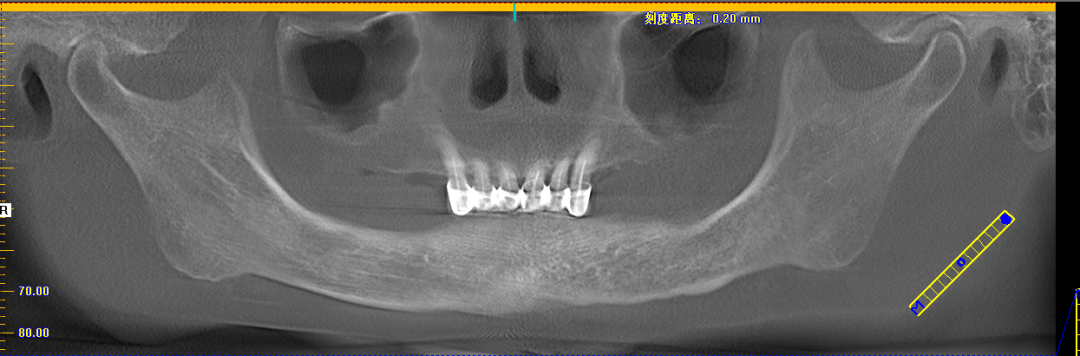

今天活动上有一位这样特殊的分享嘉宾——赖女士,今年69岁,需要种植的是下半口。赖女士为了想种好牙辗转了好几家医院,因为她的右边牙龈和舌头是连在一起的,去过其它医院说要割开才能种牙,后来打听到麦芽口腔姚院长临床经验丰富,过来看诊后,给出的主案可以用数字化导板进行种植牙,并不用割开原本连在一起的牙龈和舌头,赖女士听到此方案相当满意。

姚江武院长来为大家分享顾客术前牙片情况及种植方案。并现场讲解数字化全程导板种植技术与传统种植牙的区别和优势。